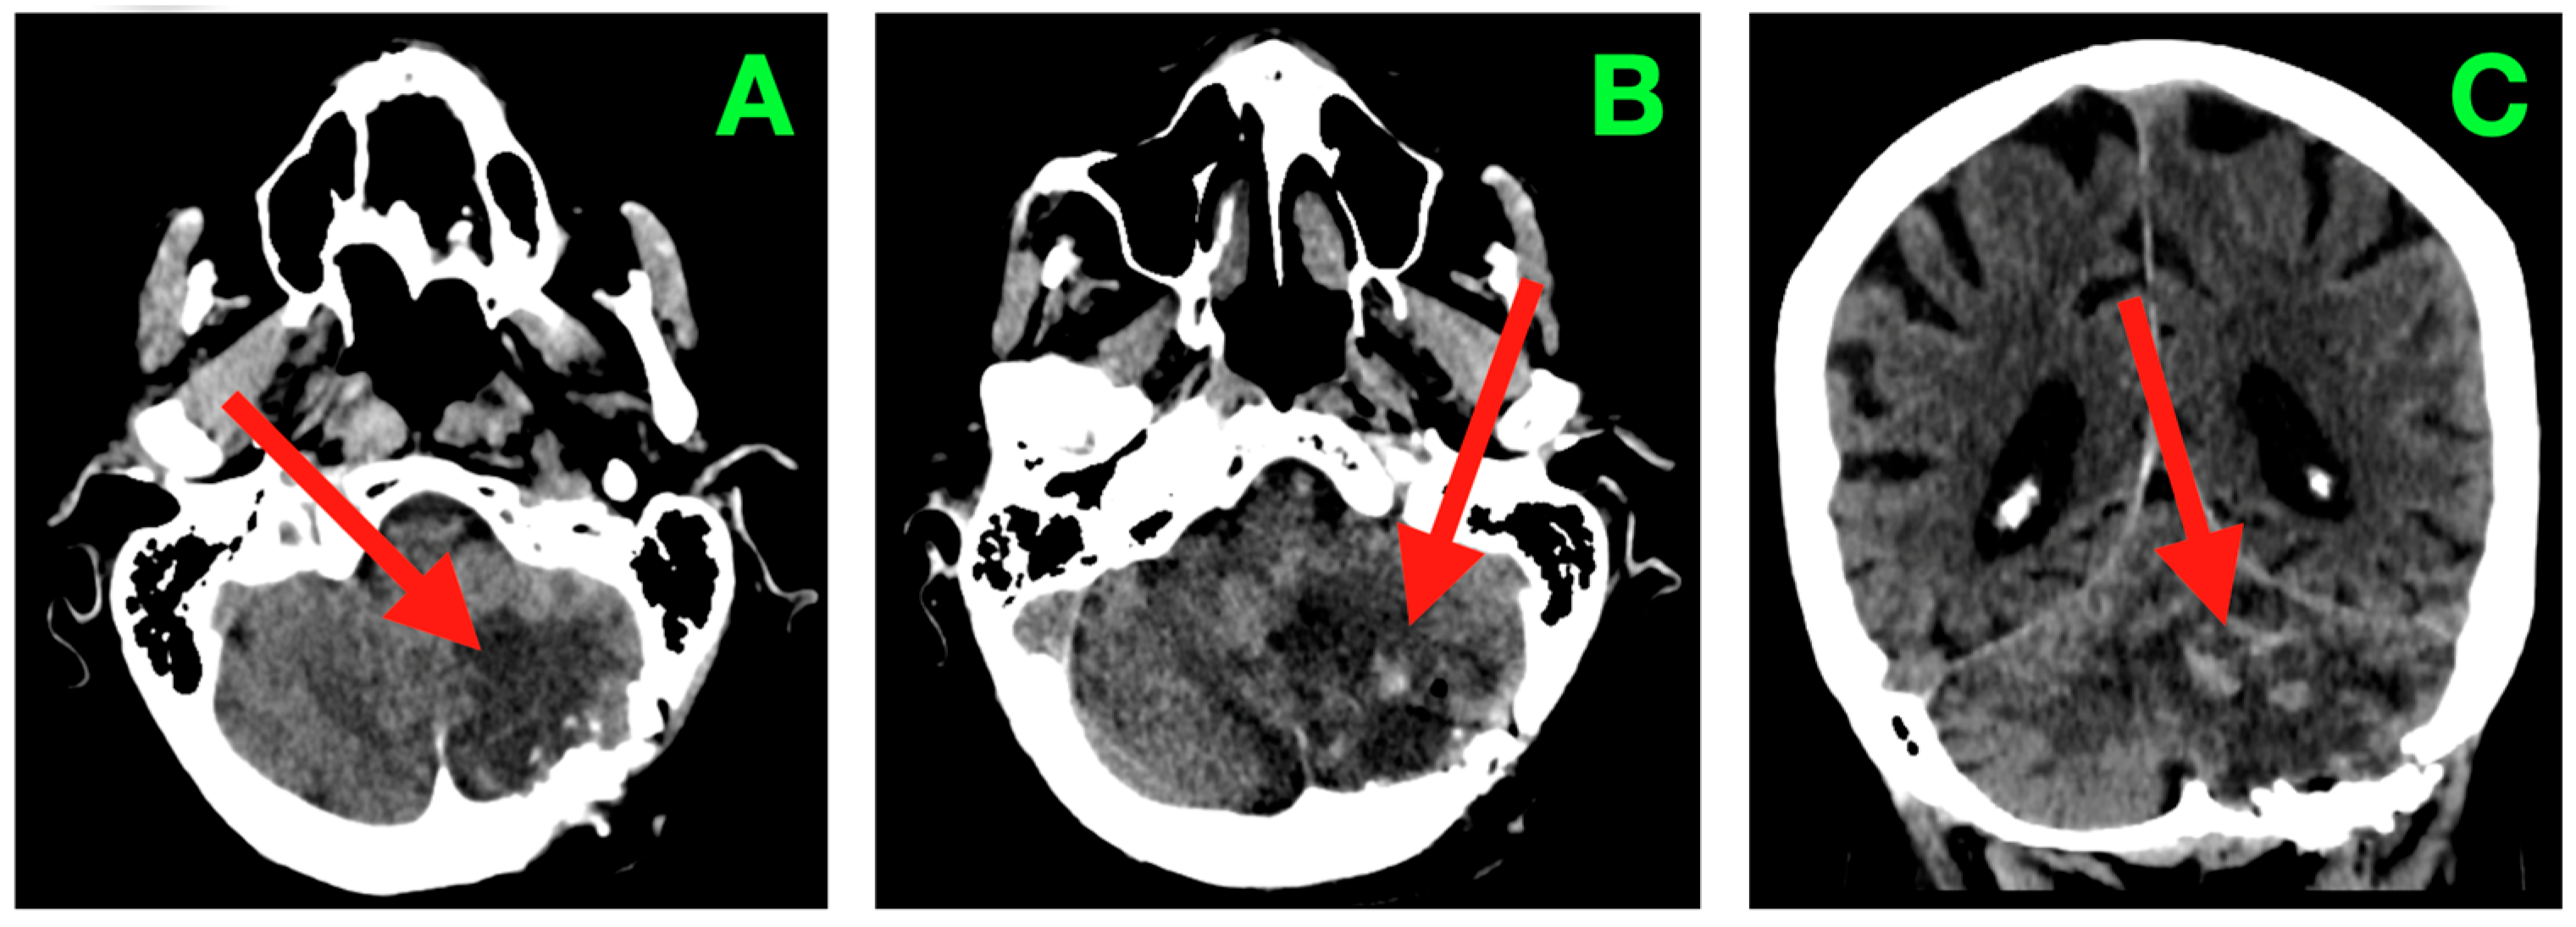

2. Case Presentation